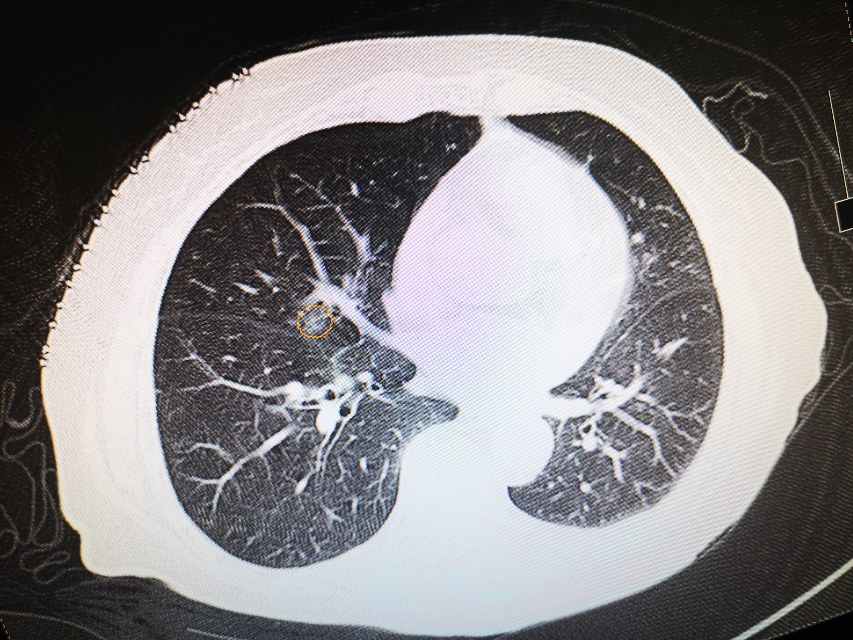

接过CT片,李医生仔细分析起来。果然又是一例顽皮的肺磨玻璃。只见,在右肺中叶外侧段,一个8mm的混合磨玻璃结节,躲藏在封闭的房间内,也就是我们常常说的密室。密室的外墙是右肺中叶肺动脉、中叶支气管、斜裂胸膜,门是中叶分支动脉。通往密室的是斜裂和右肺中叶动脉和支气管形成的一个小通道。好在还有路径可以通过!老话说谨言慎行,一点没错😂,不过谁让咱是江湖兵器排行前十的小李飞针呢,为了最小的创伤解决患友的疾苦,咱们必须不畏艰难,知难而进,迎难而上!将密室中的磨玻璃结节消灭!